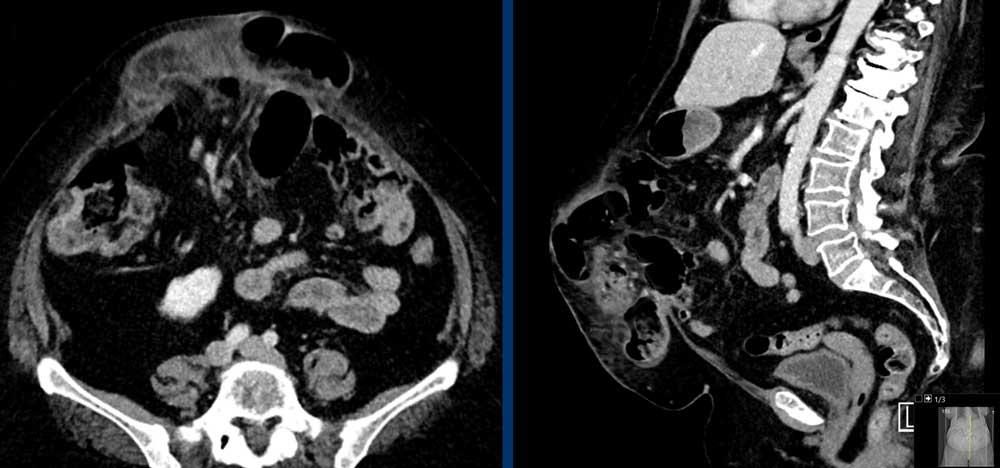

Các hình ảnh này thuộc về một bệnh nhân nữ 78 tuổi, béo phì nặng, có thoát vị thành bụng đường giữa sau phẫu thuật.

Hãy nghiên cứu các hình ảnh này, sau đó so sánh với các hình ảnh tiếp theo được chụp một tháng sau, khi bệnh nhân nhập viện với khối thoát vị sưng đau.

Hiện tại đã xuất hiện các dấu hiệu của thắt nghẹt, cụ thể là:

- Dấu hiệu phân trong ruột non mới xuất hiện, thấy rõ nhất trên các lát cắt ngang (mũi tên trắng).

- Thâm nhiễm mỡ mạc treo (mũi tên đen).

Cũng như bất kỳ trường hợp thoát vị nào có chứa ruột, tình trạng thắt nghẹt trong thoát vị thành bụng xảy ra do hậu quả của tắc ruột quai kín kèm nhồi máu tĩnh mạch.